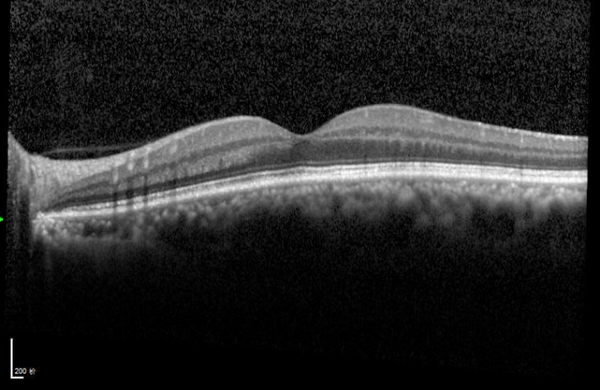

短短十五天后复查,陈先生的左眼视力已从术前的0.1显著提升至0.4!通过OCT(光学相干断层扫描)等精密设备检查发现,其黄斑水肿已消退,视网膜结构层次变得清晰。